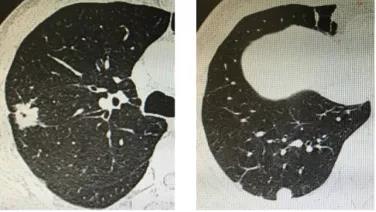

肺部结节是肺内发生的圆形或类圆形的异常病变组织,直径≤30mm,由于病变比正常充气肺泡密度高,故在胸片中显示为阴影,在CT中表现为结节,而直径小于10mm的称为肺部小结节,肺部结节可能是良性病变(如疤痕、炎症、结核、良性肿瘤等)或恶性病变(如癌前病变、原位癌、原发性肺癌或肺内转移癌等),肺结节因表现的多样性、不典型性,确诊有一定难度。